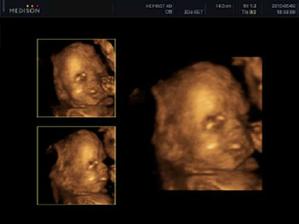

Naše prvé tehotenstvo